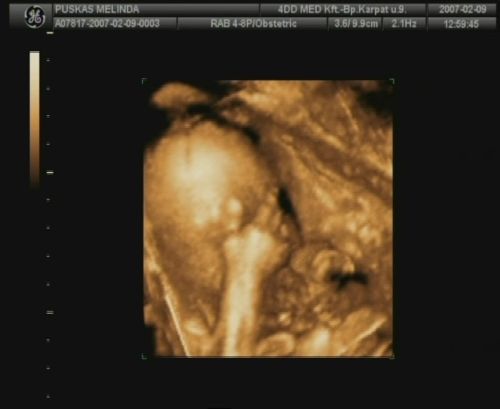

Sziasztok, megjöttem a 4D-ről. Sajnos most nincs időm a dvd-ről kimentegetni a képeket, de a telcsivel azt a hármat lefotoztam, amit kaptunk, remélem, hogy kivehető lesz azért számotokra a lényeg!

A szülésem dátuma is 2007.05.25.-re módosult, illetve a tickeremet is átjavítottam esszerint! :)

Ja lányok, csak, hogy untassalak titeket, tegnap az egyik barátom megmutatta, hogy kell dvd felvételről kimenteni képeket, így Domcsiról lementettem pár tuti képet! Mellékelem, remélem nem baj:

Untatni? édes képekkel lehet szerinted minket untatni? Ezek nagyon cukik! Édes nagyon a babád!

Az ásítós, meg az első, a szemvakargatós, az igen :)

olyan mintha azt akarná mondani, hogy minek keltettetek fel, hát hagyjatok már békén, itt már aludni se lehet?

Hát nagyon cuki, az ilyen képekkel nem lehet betelni :)